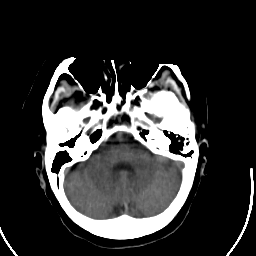

Stroke CT #2 -- Slice #5

[Home][Help][Clinical] Slice 5